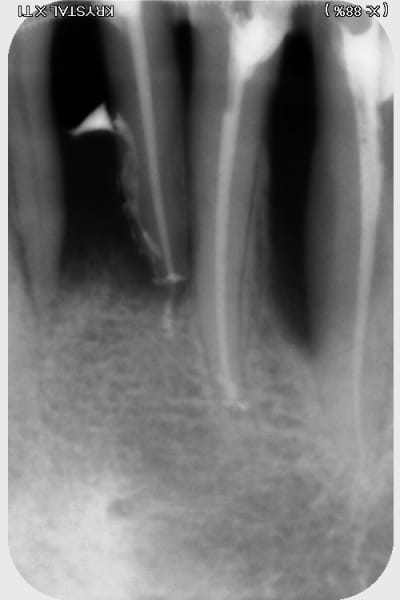

j'ai trouvé ça...rien de parfait malgré l'utilisation de broches manuelle, en alternance avec les rotatives sur certaines racine "légèrement coudées"....

pano et scan plus tard